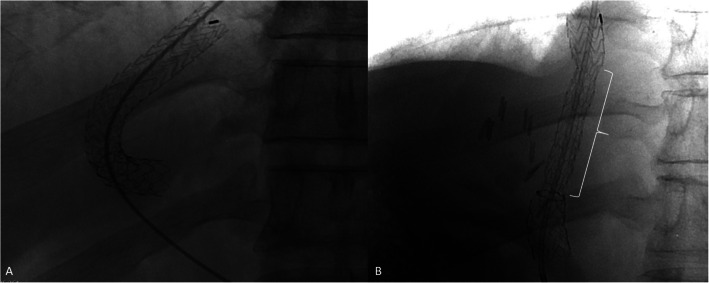

Purpose: Assess incidence of hepatic encephalopathy (HE) after transjugular intrahepatic portosystemic shunt (TIPS) in patients treated with 8-10 mm Controlled Expansion diameter VIATORR® (VCX) versus 10 mm diameter first-generation VIATORR® (Legacy) stent-grafts.

Materials and methods: Single-centre retrospective study (January 2015 to March 2024), including 132 adult patients with cirrhosis treated with TIPS due to complications of portal hypertension. Outcomes included post-TIPS new onset overt HE, ascites response, re-bleeding, mortality and portal pressure gradient (PPG) before and after TIPS. Comparisons used Chi square and Fisher´s exact test for categorical variables and Student´s t test or Mann-Whitney test for quantitative variables.

Results: Indication for TIPS was refractory ascites (n = 82) and variceal bleeding (n = 50). The VCX group (n = 85) and the Legacy group (n = 47) had similar new onset overt HE: 37% (31/85) vs 43% (20/47), respectively (p = 0.31); mortality rates (34% [29/85]) vs 39% [18/47], respectively, p = 0.57) and re-bleeding (17% [6/35] vs 20% [3/15], respectively, p = 1.00). Median PPG reduction after TIPS was 10 mmHg (7 - 13) in the VCX group and 12 mmHg (9 - 15) in the Legacy group (p = 0.02). Subgroup analysis revealed post TIPS overt HE rate of 38% (19/50) in the VCX group vs 53% (17/32) in the Legacy group (p = 0.13), with refractory ascites as an indication. Shunt dysfunction rate was 7% (6/85) in the VCX group (stent thrombosis n = 6, stenosis or malpositioning n = 0) and 0% (0/47) in the Legacy group (p = 0.09).

Conclusion: VCX stent grafts induce an immediate lower PPG reduction, which might lead to more stent dysfunctions, but also to a reduction in post-TIPS HE.